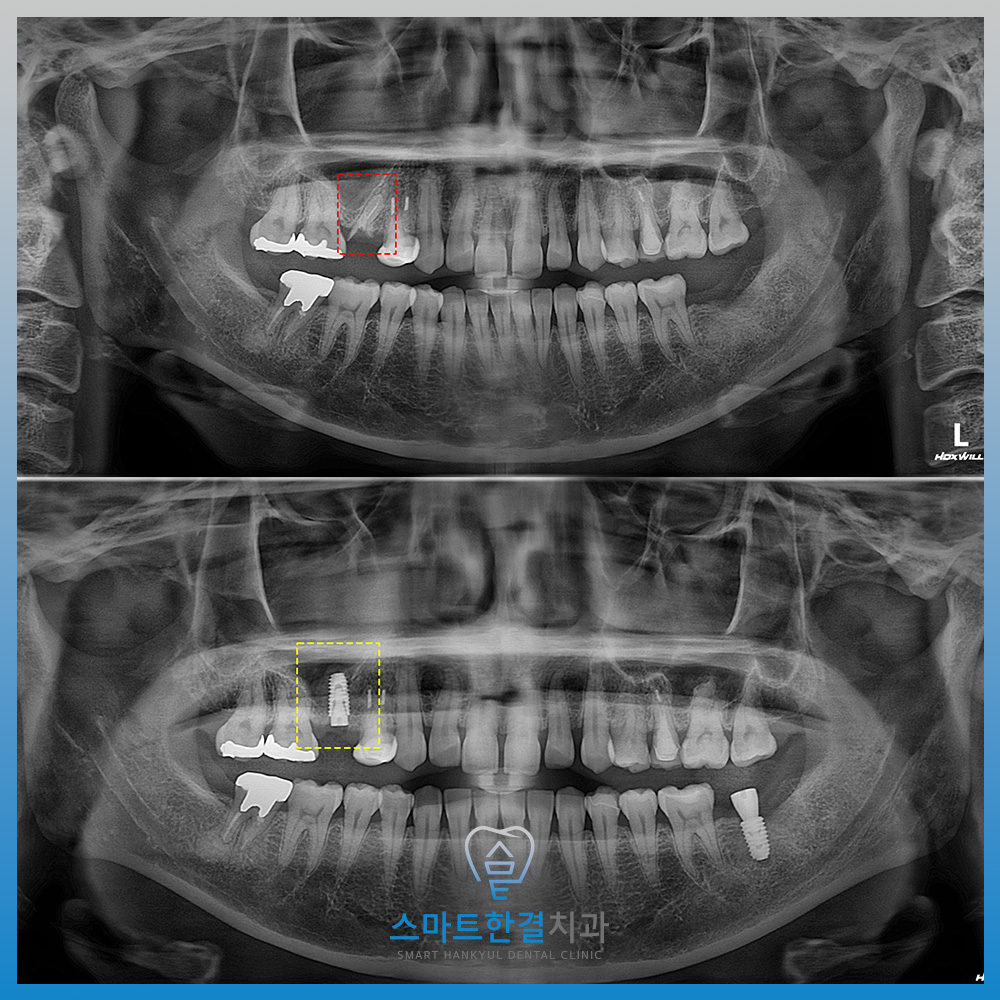

화서동치과 스마트한결치과의

임플란트 수술 전후 사진이에요.

환자분께서는 임플란트 식립뿐만 아니라

상악동거상술까지 진행해야 돼서

무섭고 불안해하셨으나,

수술하면서도 불편함 없으시고

이후에도 괜찮으셔서 다행이라며

만족해 주셨어요.

현재까지 임플란트와 상악동 부위 모두

안정적인 상태를 유지할 수 있었답니다.